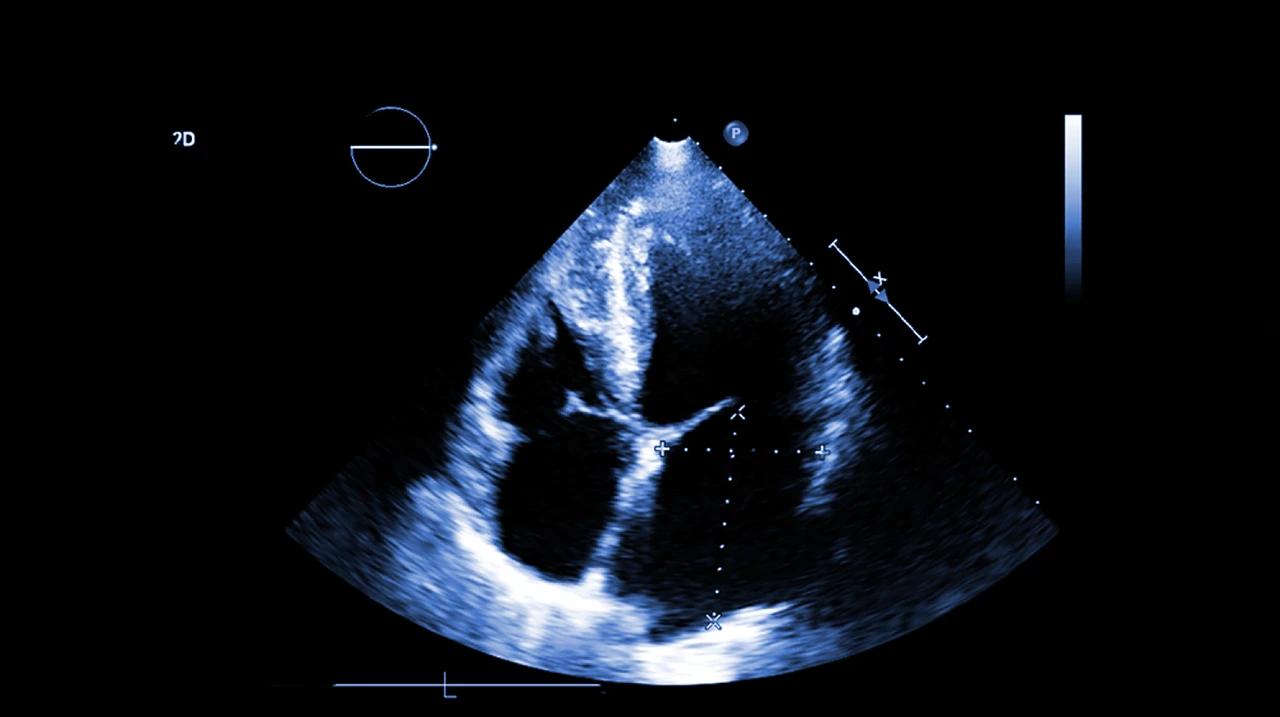

• Ecocardiograma: usa ultrasonido para observar la estructura y el movimiento del corazón

Estudio de ecocardiograma, como estudio de imagen para la detección de los diferentes problemas cardíacos que puede presentar una persona.